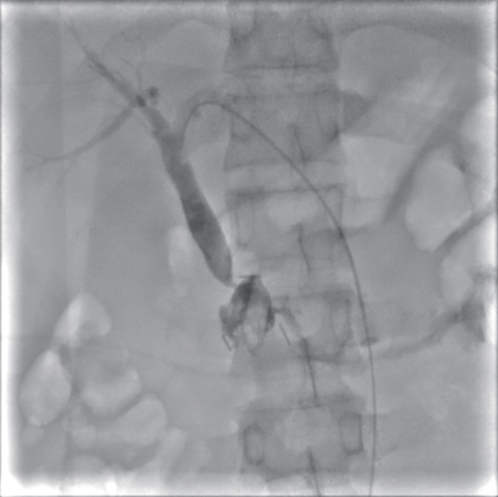

• Duodenum-preserving pancreatic head resection, also known as Beger surgery, has a high incidence rate of bile duct injury after surgery, while the treatment modality for bile duct injury depends on the severity of the injury, and endoscopic therapy is often challenging in case of severe bile duct injury. Recently a patient with biliary fistula after Beger surgery was admitted to Affiliated Hangzhou First People’s Hospital, Westlake University, and successful diagnosis and treatment were achieved through oral choledochoscopy-assisted percutaneous-endoscopic rendezvous technique.